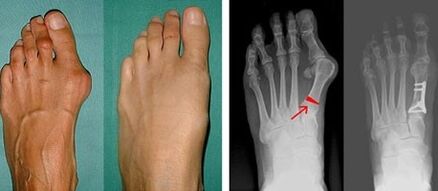

İlk ayak parmağındaki Valgus deformitesi çoğunlukla olgun yaştaki kadınları etkiler, ancak aynı zamanda erkekleri de etkiler. Başparmağın deforme olmuş tabanı estetik açıdan hoş görünmüyor. Bu durumda kişi fiziksel rahatsızlık hisseder ve ileri aşamada ağrı hisseder. Ayak başparmağının sapması, ayaktaki eşit olmayan vücut yükünün sonucudur. Bu tür değişikliklerin ayaklar ve diğer parmaklar üzerinde zararlı etkisi vardır.

Ayak başparmağı ve küçük ayak parmağının valgusunu tanımlamanın ilk aşamasında doktor görsel bir muayene yapar. Bu sayede patolojinin gelişim aşamasını belirler. Eklemlerdeki ayrıntılı değişiklikleri tespit etmek için röntgen ve plantografi reçete edilir.

Eğer görsel muayene ve röntgenlerden sonuç alınamazsa hasta olası düztabanlığın tespiti için plantografiye yönlendirilir. Bu yöntem, hasta için ortopedik özelliklere sahip ayakkabı veya tabanlıkların yapıldığı ayak izlerinin alınmasını içerir. Daha sonra hastaya podometri reçete edilir. Bu yöntem, bir kişinin ağırlığının ayaklar üzerindeki basıncını belirlemek için bilgisayar analizini kullanır. Gelişmiş teşhisin sonuçları, birinci ve ikinci ayak parmağının eğriliği için bir tedavi yöntemi seçmenin temelini oluşturur.